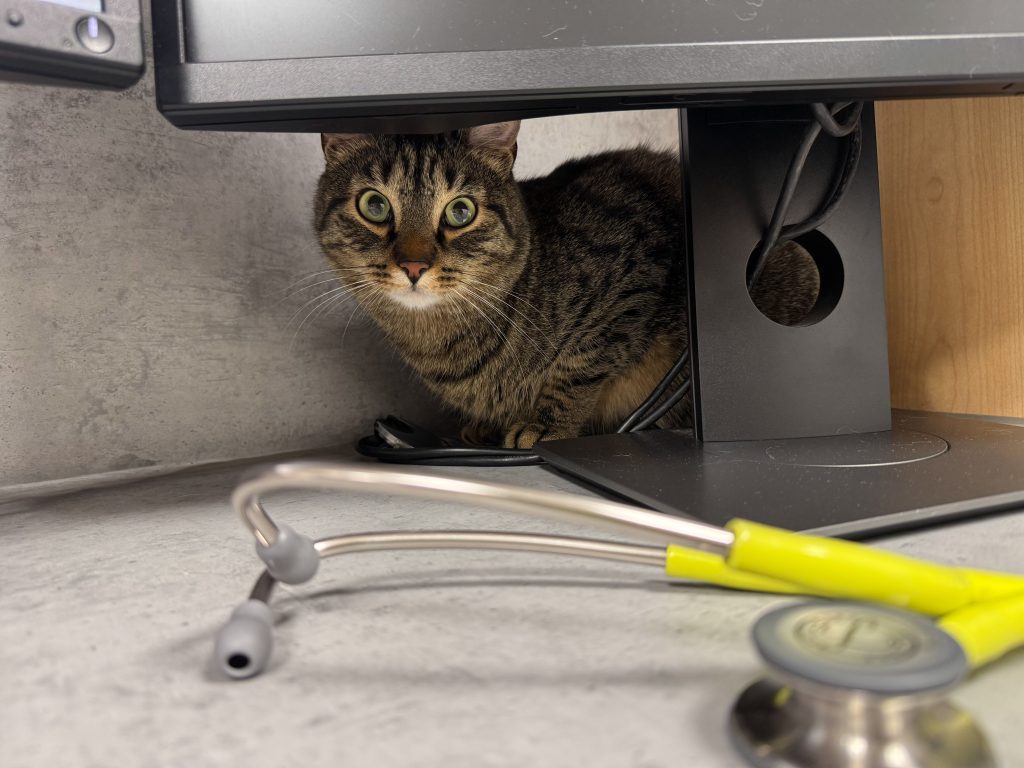

Choroby żołądka i jelit u psów i kotów – diagnostyka i rozpoznanie

obejmuje rozpoznawanie chorób przełyku, żołądka, jelit, wątroby, trzustki oraz innych narządów jamy brzusznej u psów i kotów. Objawy ze strony przewodu pokarmowego należą do najczęstszych przyczyn wizyt w gabinecie weterynaryjnym i mogą mieć zarówno łagodne, jak i poważne podłoże.

Precyzyjna diagnostyka pozwala odróżnić przejściowe zaburzenia trawienia od chorób wymagających leczenia farmakologicznego, specjalistycznego lub interwencji chirurgicznej.

Podstawą diagnostyki jest szczegółowe badanie kliniczne, obejmujące: